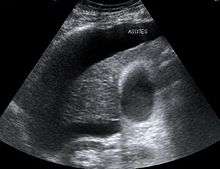

The major criteria include liver disease with portal hypertension; kidney failure; the absence of shock, infection, recent treatment with medications that affect the function of the kidney (nephrotoxins), and fluid losses; the absence of sustained improvement in kidney function despite treatment with 1.5 litres of intravenous normal saline; the absence of proteinuria (protein in the urine); and, the absence of kidney disease or obstruction of kidney outflow as seen on ultrasound.[3]